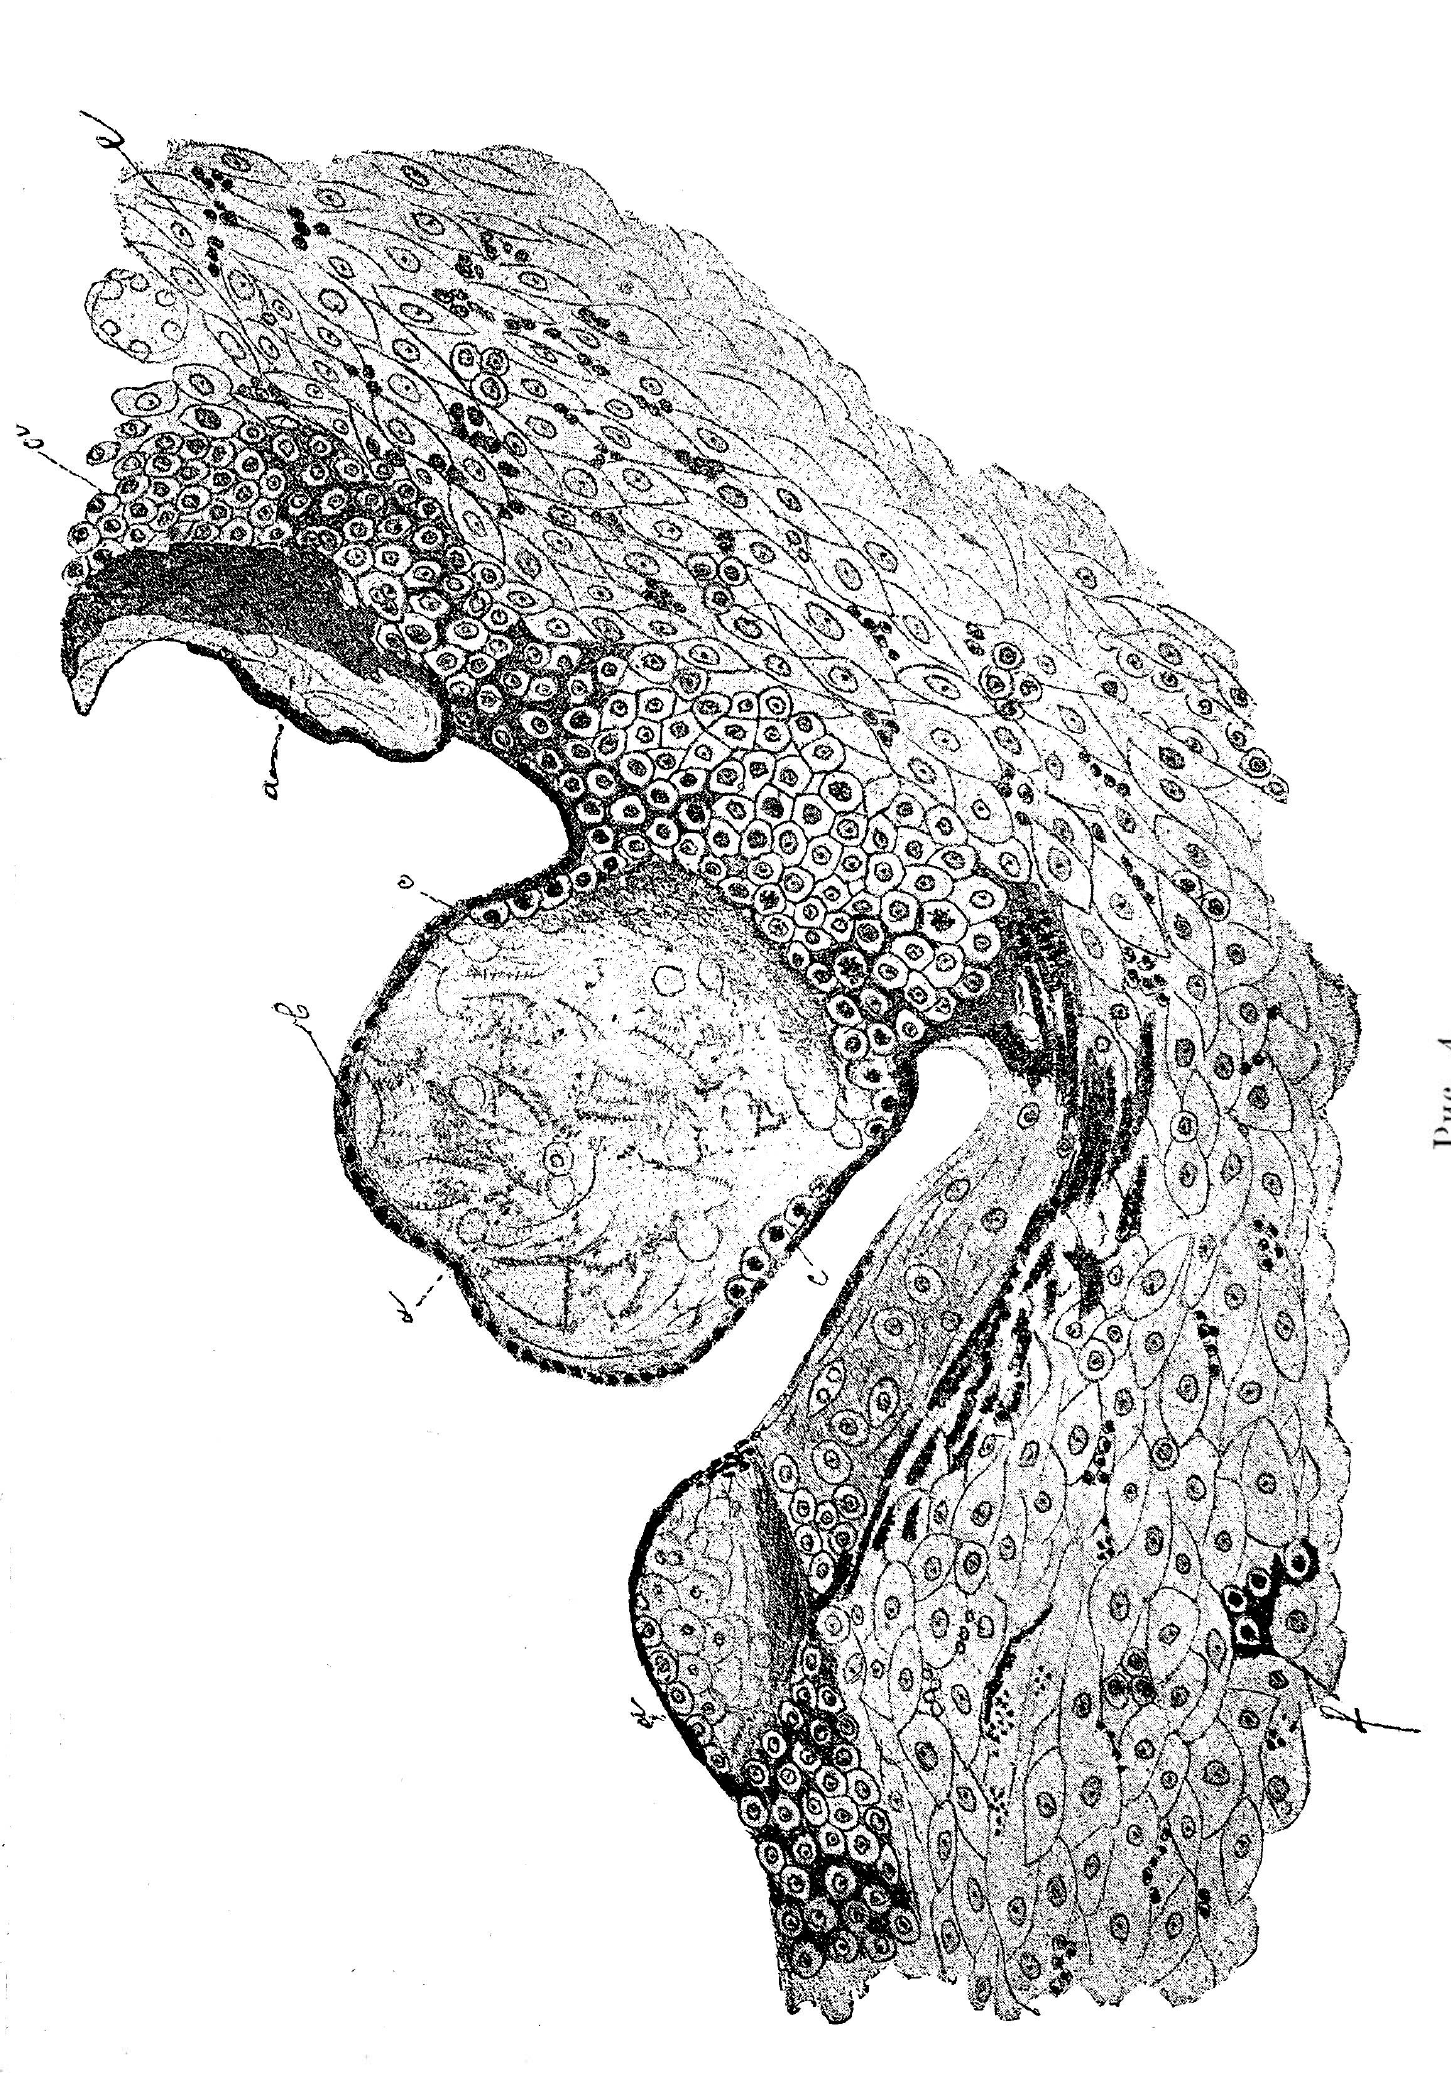

Абортъ около 2 мѣсяцевъ беременности. Обработка флеминговою жидкостью (рис. 4).

Рис. 4. Препаратъ 2 мѣсячнаго аборта: а—ворсинки chorion’a. b—syncytium s. plasmodium, c—клѣточный слой (Zellschicht) Langhans’а, d—decidua foetalis, e—decidua uterina, f—группа клѣтокъ deciduae foetalis съ прилежащею къ нимъ массою syncytium’a.

Figure: 4. Preparation for 2 month abortion: a — chorion'a villi. b — syncytium s. plasmodium, c — cell layer (Zellschicht) Langhans’a, d — decidua fetalis, e — decidua uterina, f — a group of deciduae fetalis cells with an adjacent mass of syncytium’a.

Первое впечатлѣніе, которое получается при взглядѣ на границу соединенія ворсистой оболочки съ материнскою частью placent’ы, таково, что ворсины какъ будто вростаютъ въ подлежащую материнскую decidua.

При ближайшемъ изслѣдованіи оказывается, что въ ворсинѣ происходитъ цѣлый рядъ измѣненій и что въ этомъ сліяніи наиболѣе активная роль выпадаетъ на долю ворсистой оболочки. Въ томъ отдѣлѣ ворсины, посредствомъ котораго она связывается съ материнской decidua, syncytium исчезаетъ, въ тоже время какъ клѣточный слой Langhans’а, начинаетъ усиленно пролиферировать, образуя различной величины клѣточныя разрощенія, которыя незамѣтно теряются въ материнской decidua, смѣшиваясь съ ея элементами. Ворсины густо лежатъ другъ возлѣ друга и каждая изъ нихъ въ мѣстѣ соединенія съ материнской decidua, благодаря разрощенію клѣточнаго слоя, участвуетъ въ образованіи почти сплошнаго слоя клѣточной ткани, лежащаго на границѣ между Zottenraum (межворсинчатое пространство) съ его ворсинками и материнской decidua и непосредственно переходящаго въ послѣднюю.

Образовавшаяся, такимъ образомъ, ткань совершенно идентична тѣмъ клѣточнымъ гнѣздамъ, которыя описаны выше, и при первомъ взглядѣ также похожа на материнскую decidua. Но при ближайшемъ знакомствѣ между ними оказывается существенное отличіе. Такъ какъ источникъ происхожденія этой ткани для насъ очевиденъ, таковымъ является клѣточный слой Langhans’а, составляющій неотъемлемую принадлежность ворсины, то поэтому, согласно предложенію Merttens’а, будемъ называть его decidua foetalis въ отличіе отъ decidua uterina, происшедшей изъ межжелезистой соединительной ткани слизистой оболочки матки. Decidua foetalis состоитъ изъ многоугольныхъ однообразныхъ по величинѣ клѣтокъ, съ нѣжной протоплазмой и съ крупными ядрами, въ которыхъ нерѣдко видны фигуры дѣленія. Клѣтки же deciduae uterinae весьма различны по величинѣ; послѣдняя колеблется отъ небольшой, немногимъ превосходящей величину лейкоцита и до огромныхъ размѣровъ. Какъ выше описано, онѣ имѣютъ наклонность вытягиваться и приближаются къ веретенообразной формѣ, между тѣмъ какъ клѣтки deciduae foetalis, большею частью, сохраняютъ свою полиэдрическую форму. Между ними не наблюдается никакихъ мелкоклѣточныхъ скопленій, что присуще decidua uterina. Наконецъ, какъ на особенность этого слоя (decid. foetal.) слѣдуетъ указать, что во многихъ мѣстахъ препарата между клѣтками decid. foetalis замѣчается большее или меньшее количество какой-то безструктурной массы, которая окружаетъ болѣе или менѣе то одну клѣтку, то небольшую группу ихъ (2—3 и болѣе). Часто это вещество заключаетъ въ себѣ большее скопленіе ядеръ, густо окрашивающихся сафраниномъ и фуксиномъ. Въ общемъ оно напоминаетъ собою syncytium и представляетъ, вѣроятно, ничто иное какъ метаморфизировшіяся клѣтки dec. foetalis.

Слѣдовательно, decidua слагается изъ двухъ тканей различнаго происхожденія—одна decidua uterina, возникающая изъ межжелезистой ткани слизистой оболочки матки, измѣняющейся подъ вліяніемъ новыхъ условій питанія, и другая, непосредственно сливающаяся съ нею, decidua foetalis, происшедшая изъ клѣточнаго слоя ворсинъ (ektoderm). Поверхность тѣхъ участковъ deciduae foetalis, съ которой не спаяны ворсины,, т. е. со стороны Zottenraum, покрыта также syncytium. Такимъ образомъ, стѣнка полости, въ которой находятся ворсины,— выстлана на всемъ протяженій syncytium’омъ, который замѣняетъ собою эндотелій.

Какъ упомянуто выше, нельзя усмотрѣть опредѣленной и рѣзкой границы между обоего рода decidua. Повидимому элементы deciduae foetalis цугами вростаютъ въ decidua uterina и, благодаря тому, что нѣкоторыя клѣтки материнской deciduae, болѣе молодыя, по величинѣ и формѣ весьма напоминаютъ элементы фетальнаго слоя, мы лишены возможности положить рѣзкую границу между ними. Однакоже нерѣдко сопровождающіе ихъ остатки syncytium’a позволяютъ отличить ихъ отъ клѣтокъ материнской deciduae. Такимъ образомъ, на разрѣзахъ онѣ располагаются въ decidua uterina или въ видѣ отпрысковъ, исходящихъ изъ слоя dec. foetalis или образуютъ различной величины группы и островки полигональныхъ клѣтокъ, располагающихся среди decid. uter. Фибринознаго слоя Нитабухъ, признаваемаго Reinstein-Mogilowa и другими, какъ постоянную границу между обѣими decidua, я не могла констатировать. Въ болѣе позднія стадіи беременности подобный слой встрѣчается, но никогда не бываетъ непрерывнымъ.